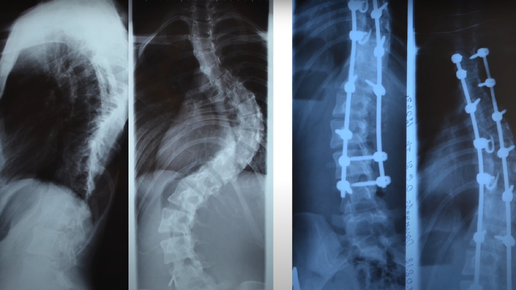

"Увеличилась в росте на 10 см" после лечения сколиоза 4-ой степени

Родители девочки искали нашу клинику три года и наконец обратились к нам. Мы подробно объяснили, какой проведём объём работ, как будет выполняться операция, каким будет результат и сразу получили согласие на лечение...